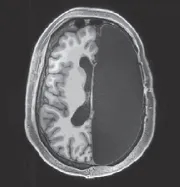

Working patiently over the course of several hours, the surgeon removed half of the delicate pink material that underpinned Matthewâs intellect, emotion, language, sense of humor, fears, and loves. The extracted brain tissue, useless outside its biological milieu, was banked in small containers. The empty half of Matthewâs skull slowly filled up with cerebrospinal fluid, appearing in neuroimaging as a black void.2

Half of Matthewâs brain was surgically removed.